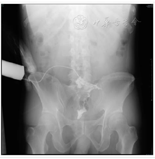

立位腹平片提示OTSC夹在位,并于2天后复查患者窦道造影提示原窦道已较OTSC治疗前明显减小,但仍可看到少量造影剂经内瘘口进入乙状结肠肠腔内,为促进肠瘘进一步愈合,遂经皮肤外瘘口注入纤维蛋白胶充填瘘管,封堵瘘口。加强外瘘口持续换药,并继续应用禁食、抑酸、肠外营养支持治疗2周后,复查腹部CT提示瘘口周围组织未见明显渗出(图6),逐步过渡为经鼻胃管肠内营养支持治疗,考虑患者病情稳定,予以办理出院,实行家庭肠内营养支持治疗。